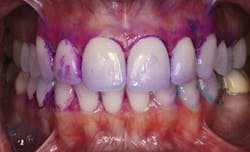

Bacterial testing is also available to test for the presence of Streptococcus mutans and Lactobacillus.19 Although these tests are useful, it may also be time-consuming for a dental hygienist to implement this type of testing on every patient. The dental hygienist is the ideal dental practitioner to evaluate the presence, location, and amount of plaque and calculus on the teeth. In addition, a disclosing agent (see Fig. 1) designed to detect acidogenic dental plaque (see Fig. 2)20 may be an efficient, cost-effective alternative.